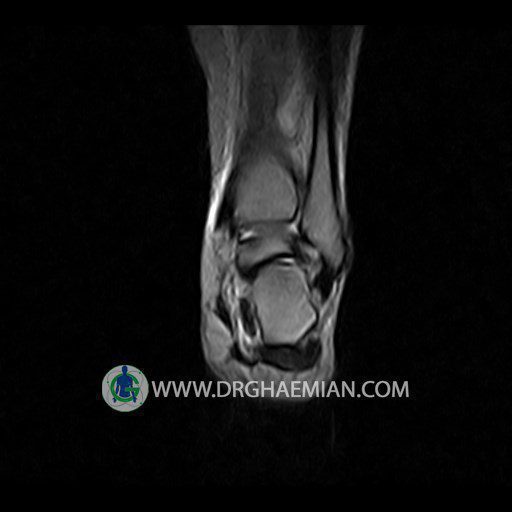

پزشکان اغلب از تصویربرداری ام آر آی برای تشخیص و درمان عارضه های پزشکی که فقط با استفاده از اشعه ایکس یا میدان مغناطیسی و امواج رادیویی قابل مشاهده است، استفاده می کنند. دستگاه ام آر آی تصاویر دقیق از ساختار های داخلی بدن ایجاد می کند. در این کیس تورم مچ پا بیمار مشاهده می شود.

Technique: Sagittal T1, T2 , Axial GE , coronal & sagital fatsat .